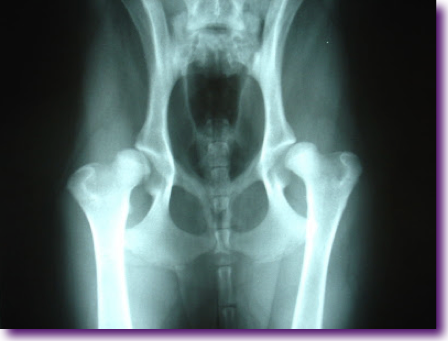

La displasia de cadera aparece cuando al finalizar el desarrollo de la articulación coxofemoral, el acetábulo cotiloideo y la cabeza femoral no concuerdan mutuamente entre sí en su forma. Esta no concordancia pude ser debida, en primer lugar, a un acetábulo plano, con lo que se dificultará la sujeción de la cabeza femoral, y aparecerá una sobrecarga tanto en el cartílago de la cabeza del fémur como en el del acetábulo, produciéndose una osteoartritis. Si en lugar de una acetábulo plano nos hallamos ante una cabeza de fémur demasiado pequeña o no esférica, se darán las mismas cargas desiguales produciéndose los mismos cambios degenerativos.

Los procesos artrósicos, las exostosis óseas, la presencia de osteofitos, la perdida de congruencia y la mala conformación articular determinaran la gravedad de la DC. Se ha intentado valorar al máximo las conformaciones anatómicas de las estructuras óseas para poder precisar al máximo -incluso sin existir degeneración de cartílago- la existencia de la lesión. Además, debemos tener en cuenta las diferencias en la morfología ósea que se da.